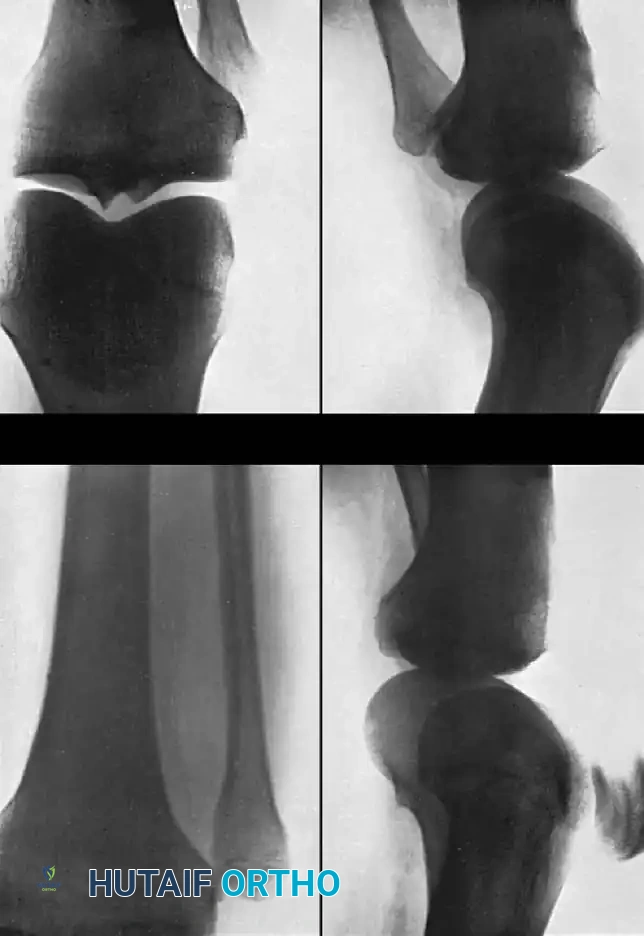

Dislocation of the knee has historically been considered a rare orthopaedic emergency; however, contemporary trauma registries suggest its frequency has increased significantly over the years. In a seminal report of 22 knee dislocations, Kennedy implied that the true incidence is likely much higher than recognized. This discrepancy occurs because many knee dislocations spontaneously reduce or are reduced by emergency medical personnel at the scene of the injury without subsequent accurate reporting of the initial dislocated state.

Knee dislocations are highly morbid injuries that threaten the viability of the limb due to their intimate association with the popliteal artery and peroneal nerve. They are designated directionally as anterior, posterior, medial, lateral, or rotary, strictly according to the displacement of the tibia in relation to the femur. Rotary dislocations are further subclassified as anteromedial, anterolateral, posteromedial, and posterolateral.

Initial Evaluation and the Irreducible Dislocation

The immediate priority in any suspected knee dislocation is a diligent neurovascular evaluation. The popliteal artery is tethered proximally at the adductor hiatus and distally at the soleus arch, making it highly susceptible to intimal tear, transection, or thrombosis during extreme tibial displacement.

While most knee dislocations can be managed with closed reduction under conscious sedation in the emergency department, closed reduction may be impossible in certain rotary variants, especially when the dislocation is posterolateral.

Blocking of concentric reduction by the interposition of the joint capsule has been classically described by Watson-Jones and Anderson. Furthermore, the "buttonholing" of the medial femoral condyle through a longitudinal tear in the medial joint capsule has been well-documented by Brennan et al., as well as by Quinlan and Sharrard. Shields et al. further noted that a torn tibial collateral ligament (MCL) and the pes anserinus tendons can also invaginate into the joint space, physically blocking reduction.

Surgical Warning: A classic clinical sign of an irreducible posterolateral knee dislocation is the "dimple sign"—a transverse skin furrow or puckering over the medial joint line caused by the medial femoral condyle buttonholing through the medial capsule. Attempting forceful closed reduction in the presence of a dimple sign is contraindicated and may cause iatrogenic skin necrosis or further chondral damage.